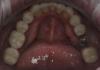

Art 7 Опубликовано 23 ноября, 2012 Автор Поделиться Опубликовано 23 ноября, 2012 откорректировал,зафиксировал низ 1 Ссылка на комментарий

IvanK Опубликовано 23 ноября, 2012 Поделиться Опубликовано 23 ноября, 2012 (изменено) откорректировал,зафиксировал низсейчас закидают тапками, потому как без коффердама.. а есть фото без цемента? И фото улыбки? Изменено 23 ноября, 2012 пользователем IvanK Ссылка на комментарий

Art 7 Опубликовано 23 ноября, 2012 Автор Поделиться Опубликовано 23 ноября, 2012 фото без цемента виниров и коронок?без коффера,с ретракцией и фумкой. кофер пока не освоил.фото улыбки сделаю когда заклею верх.)) но он как то не очень позирует)) Ссылка на комментарий

IvanK Опубликовано 23 ноября, 2012 Поделиться Опубликовано 23 ноября, 2012 фото без цемента виниров и коронок?без коффера,с ретракцией и фумкой. кофер пока не освоил.фото улыбки сделаю когда заклею верх.)) но он как то не очень позирует))Я не ортопед, может что-то не так понимаю, тогда сразу прошу прощения на 3 с конца фото цемент "повылазил" ? Ссылка на комментарий

Art 7 Опубликовано 23 ноября, 2012 Автор Поделиться Опубликовано 23 ноября, 2012 нет это база от спидекса,чтобы коронки держались на культях. Ссылка на комментарий